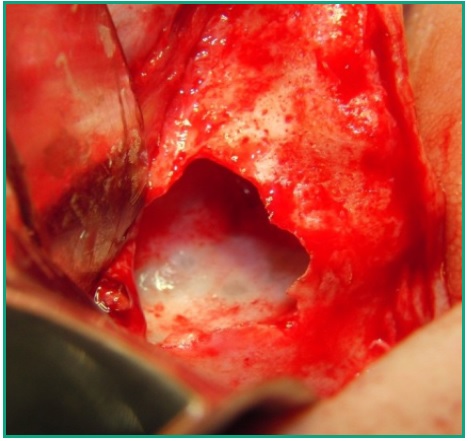

Se procede a hacer ostectomía con instrumental rotatorio y abundante irrigación con suero fisiológico, con la finalidad de agrandar la fenestración para facilitar la visibilidad. Con curetas de elevación sinusal se realiza la eliminación total de la lesión mediante la técnica de enucleación y curetaje, procediendo luego a hacer la exéresis del tabique óseo que divide dicha patología (Figs. 7, 8, 9). Por último se realizó un cierre mediante sutura continua con nylon 5 cero (Fig. 10).